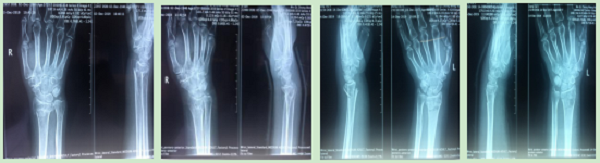

12月份门诊诊疗病例116人次,病种多为腰椎间盘突出症、腰椎管狭窄症、梨状肌紧张综合征、颈椎病、肘管综合征、胸腰椎小关节紊乱症、膝关节骨性关节炎、膝关节滑膜炎、肩关节周围炎、股骨头坏死、距骨坏死、指骨骨髓炎、丹毒、痛风性关节炎及桡骨远端骨折、肱骨骨折、股骨颈骨折、踝关节骨折、掌骨骨折、指骨骨折、跖骨骨折、趾骨骨折、肩关节脱位、指间关节半脱位等。

手法整复桡骨远端骨折、肱骨骨折、踝关节骨折、掌骨骨折、指骨骨折、跖骨骨折及肩关节脱位、桡骨小头半脱位等各类骨折脱位十余例,行小夹板固定及石膏托外固定十余例。

参与完成髋关节置换术、尺神经前置术、跟骨骨折钢板螺钉取出术、尺桡骨骨折钢板螺钉内固定取出术、掌骨骨折钢板螺钉取出术及清创缝合术等手术六例。